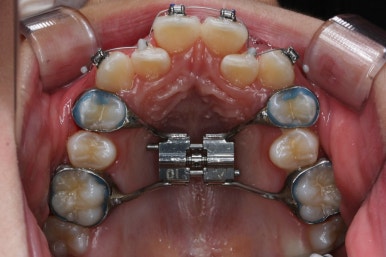

이 후에 장치를 부착하여 치아를 가지런하게 해주기 시작합니다.

장치 부착 후에는 급속도로 치아가 가지런해지기 시작합니다.

점점 가지런해지고 있는 모습이 보이실 것입니다.

악궁 확장 이후 확보된 공간은 가지러낳게 하는데 수월함을 줍니다.

악궁확장장치는 유지기간 이 후 다 제거가 되었고, 치아들이 매우 가지런해지는 것을 볼 수 있습니다.